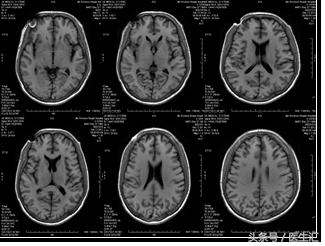

头部、腹部MRI 示双侧副鼻窦炎,肝硬化、脾大、门脉高压症(如下图)。